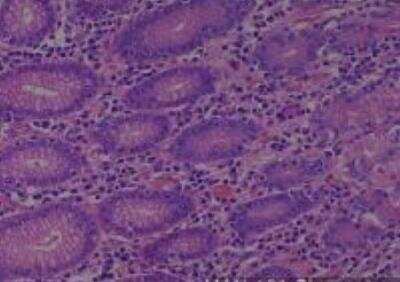

Scientific Data Images for Human Multi Tissue MicroArray (Normal Adjacent)